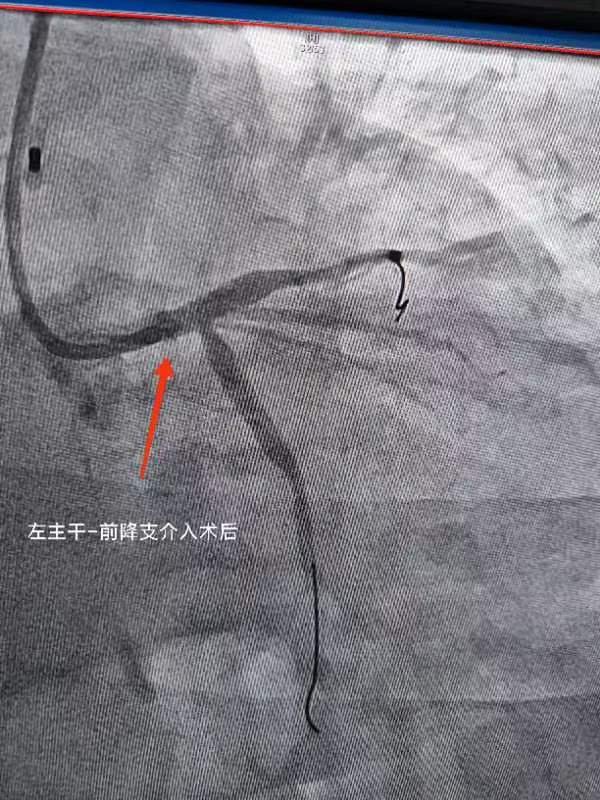

第二例患者主诉活动后气短,休息后好转,无胸痛、胸闷,运动耐量渐进性下降。经冠脉造影提示左主干严重病变,此类病变特点一旦发生急性冠脉事件,往往命悬一线,非常凶险,很多时候来不及到医院抢救。

经及时介入治疗并在 IVUS(血管内超声)验证后,临床症状明显好转,运动耐量恢复。